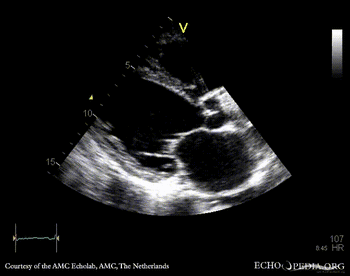

PLAX: dilated left ventricle, poor function, vegetation on aortic valve PLAX with zoom: vegetation on aortic valve